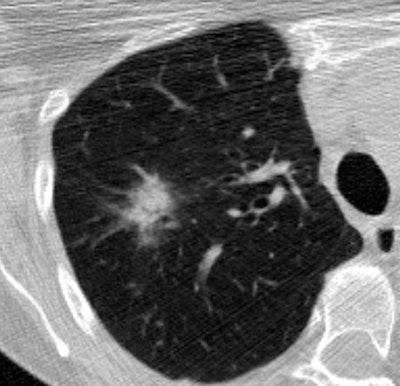

| CT image above shows extensive calcification along the carinal ridge of an airway bifurcation. The image is displayed without interpolation so that individual pixels are easily discerned. The peak voxel density along the carinal ridge shown in the slice is 614 HU. The DICOM header reveals that the CT data were acquired at 80mA, 120 kVp, 1.25-mm slice thickness, and with the bone kernel on a LightSpeed Ultra scanner (GE Healthcare, Chalfont St. Giles, U.K.). The bone kernel is not edge-enhancing, so the observed density cannot be due to the kernel; the densities were likely reduced due to partial volume artifact (the 614 HU voxel is adjacent to air). Image below from the same dataset case shows a part-solid lesion in the upper lobe of the right lung. All images courtesy of the Public Lung Database to Assess Drug Response. |